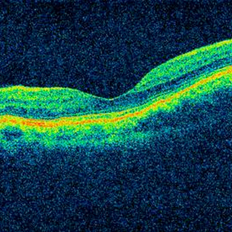

Bilateral Idiopathic Choroidal Folds - OCT Bilateral Idiopathic Choroidal Folds - OCTJan 11 2013 by Gerardo Garcia-Aguirre, MD OCT of the macula showing choroidal folds. Photographer: Gerardo Garcia-Aguirre, MD Imaging device: Zeiss Cirrus HD OCT Condition/keywords: choroidal folds